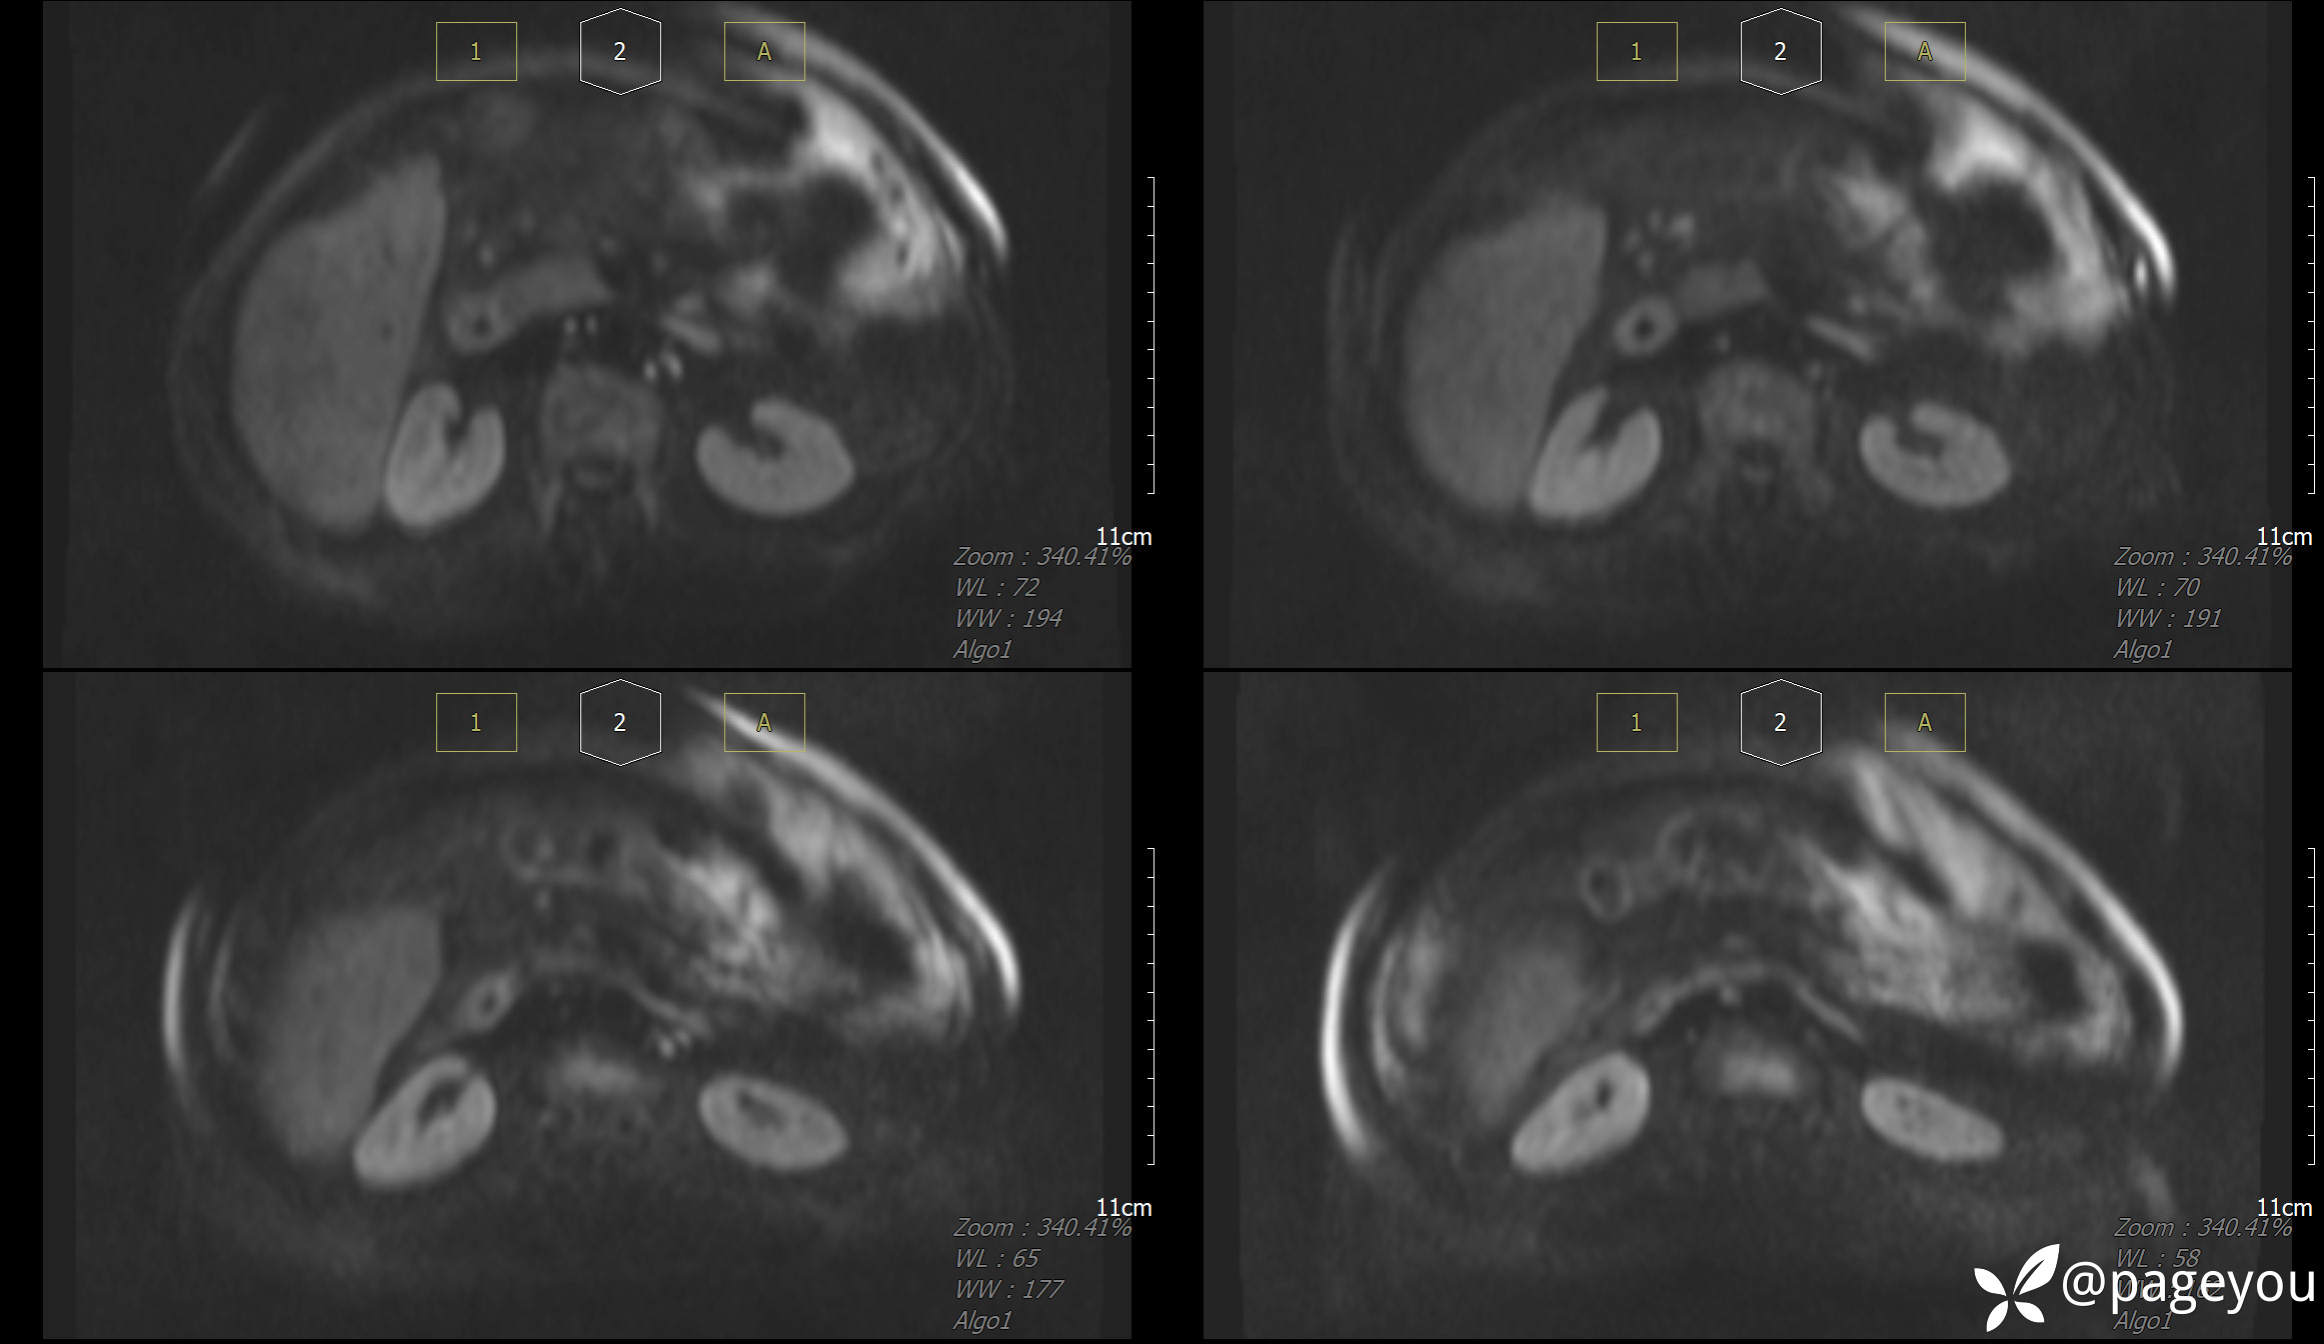

MRI检查: